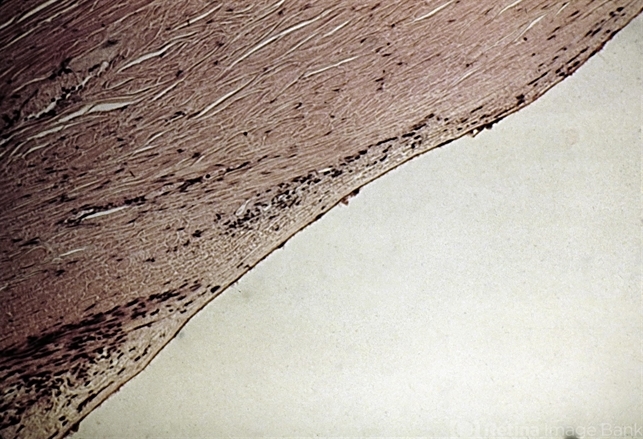

- endothelial, endothelium, descemet's membrane

- Endothelialization of the angle. Endothelium and Descemet's membrane have grown down to cover the trabecular meshwork.